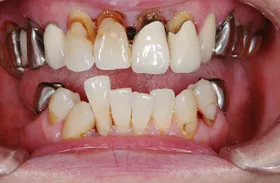

他院で「歯槽膿漏は治らない」と言われ、当院にご来院されました。歯が乱ぐいのため、歯並びもよくしたい、下は歯を既に失っているので噛めるようにもなりたい、またコーラスをされていて人前で口をあけることが多いので、できるだけ見た目を意識した治療をしてほしいとのご要望でした。

■治療前